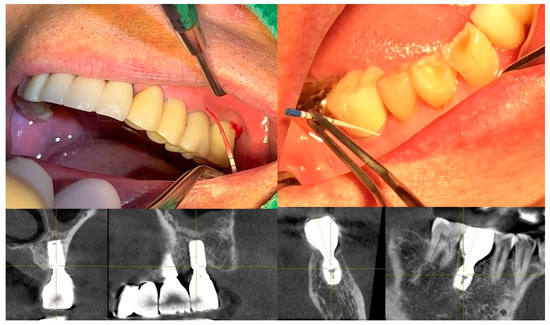

Figure 4 showcases a successful case of SPIs, demonstrating stable and esthetic outcomes. The clinical photos highlight natural soft tissue integration, while the CBCT images provide peri-implant soft tissue analysis, including measurements of transitional zone length (TZL) and soft tissue thickness (STT). These parameters help to evaluate the relationship between structural support and biological stability achieved with SPIs.

Figure 4.

Clinical and radiographic outcomes of an SPI-restored upper left first molar. Upper Two Images (Clinical Photos): Show the restored upper left first molar with well-integrated soft tissue, demonstrating a natural emergence profile and coronal flaring of the implant restoration. These features contribute to both biological stability and esthetic success. Lower Left Image (CBCT Cross-Section, Buccolingual View): Displays the implant placement. While the PCO effect suggests that the buccal margin is positioned more apically than the mesiodistal margin—resulting in a shorter overall distance from the fixture–abutment connection (FAC) to the soft tissue margin in the buccal aspect—this does not necessarily imply that the crestal zenith at the buccal side must always be positioned apically. Unlike the palatal side, where the crest may be observed at an epicrestal level, implant placement at the buccal side can still be subcrestal, provided it meets the required vertical depth for peri-implant stability or is intended to enhance the bone phenotype. Lower Right Image (CBCT with Measurements): Highlights the transitional zone length (TZL) and soft tissue thickness (STT), showing the vertical and horizontal dimensions of the peri-implant soft tissue. Additionally, it reflects the influence of the mesiodistal crestal slope (MDCS), emphasizing how ridge morphology affects implant positioning, peri-implant soft tissue stability, and overall emergence profile.